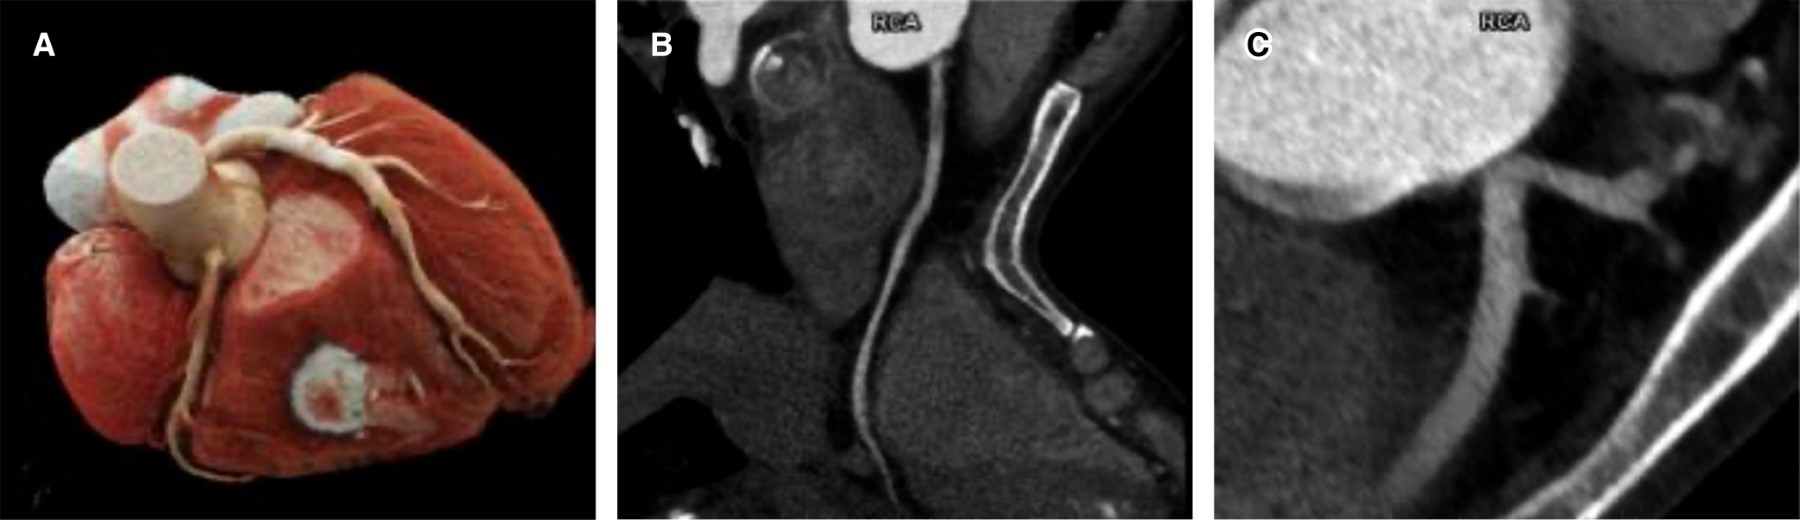

Un ostium coronario único con origen anómalo de la arteria coronaria derecha (CD) a partir de la circulación colateral de la arteria descendente anterior izquierda (DA) es una variante rara asociada con infarto del miocardio con elevación del segmento ST multiterritorial y elevada complejidad quirúrgica. Presentamos el caso de un hombre de 54 años que sufrió paro cardiaco secundario a miocarditis inducida por neumonía. La angiotomografía coronaria reveló una fístula DA-CD de 2.6 mm. La prueba de esfuerzo mostró isquemia anterior con síndrome de robo, y la angiografía coronaria confirmó la anomalía. El paciente fue sometido a revascularización exitosa de la arteria CD.

Figura 1